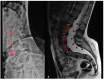

(1) Background. Scoliosis is the most common musculoskeletal manifestation of Neurofibromatosis type 1 (NF1), and it might be dystrophic (D) or non-dystrophic (ND) depending on the presence of dysplastic changes of the spine. The aim of our study was to describe the characteristics and natural history of patients with NF1 and scoliosis. (2) Methods. We retrospectively reviewed records from patients with NF1 and scoliosis. Scoliosis was classified as D if at least two dystrophic changes were documented at imaging. (3) Results. Of the 438 patients reviewed, 43 fulfilled inclusion criteria; 17 were classified in D group and 26 in ND. The groups did not differ in age and localization of scoliosis curvature. Surgery was needed more often in D group, but the between-group difference was not significant. Male-to-female ratios of 3:1 and 4:1 were reported in surgically treated NF1 patients with ND and D scoliosis, respectively. (4) Conclusions. Our data suggests independently by the presence of dysplastic changes affecting the spine that males with NF1 are more often affected by scoliosis that requires surgery.